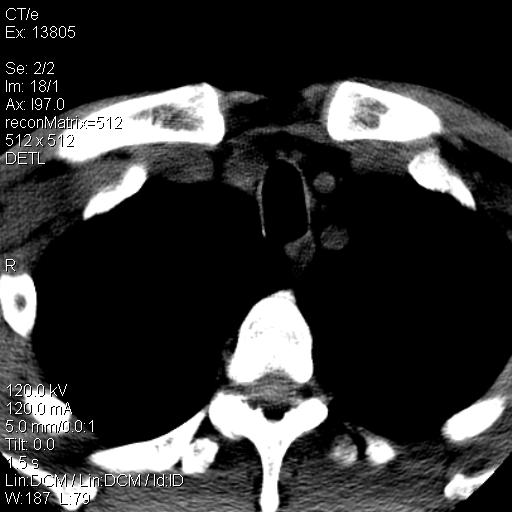

上腹部疼痛一月,呕吐10天,发现左侧颈部包快10天 胸部cr片未见明显异常。

左侧胸锁乳突肌下方、颈血管旁低密度肿块影,肿块密度尚均匀,边缘大部分清楚,邻近组织稍受压移位。考虑颈部神经鞘瘤可能性大。